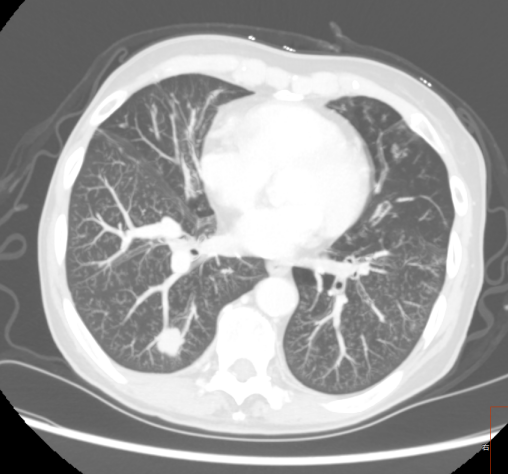

image.png

图四:部分实性磨玻璃结节

磨玻璃阴影是指肺内局限性密度增高区,边界清晰或模糊,透过该阴影仍可分辨正常肺结构,称为磨玻璃阴影(GGO)或磨玻璃结节(GGN)。对于不含软组织成分的磨玻璃状密度区,首选术语“纯磨玻璃结节”来描述。如果磨玻璃密度区含实性成分使肺结构模糊不清,则称为部分实性磨玻璃结节。在文献中,纯磨玻璃结节和部分实性磨玻璃结节被归类在亚实性结节中。